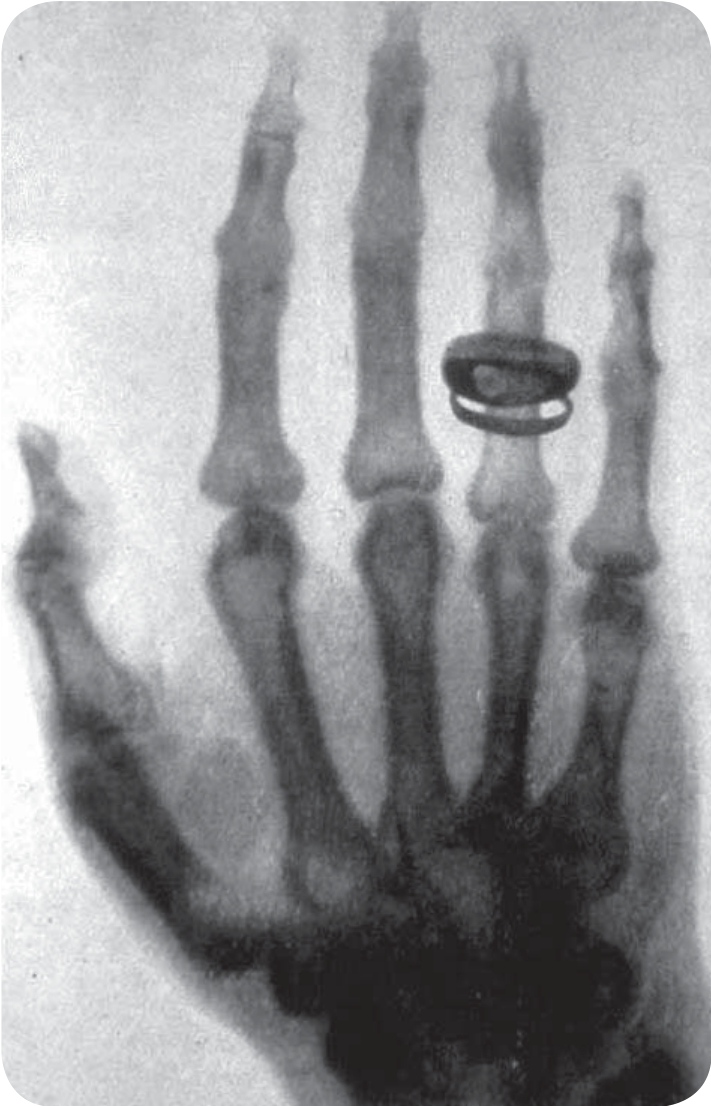

X射线照射下的手指骨头和结婚戒指的影像

X射线首先是由伦琴发现的。1895年伦琴做过一次放电实验,他事先用锡纸和硬纸板把各种实验器材都包裹得严严实实,并且用一个没有安装铝窗的阴极管让阴极射线透出。可是现在,他却惊奇地发现,对着阴极射线发射的一块涂有氰亚铂酸钡的屏幕发出了光,而放电管旁边这叠原本严密封闭的底片,现在也变成了灰黑色——这说明它们已经曝光了!他想:底片的变化,恰恰说明放电管放出了一种穿透力极强的新射线,它甚至能够穿透装底片的袋子。不过目前还不知道它是什么射线,于是取名为“X射线”。接着,他尝试着拿一些平时不透光的较轻物质,比如书本、橡皮板和木板放到放电管和屏幕之间去挡那束看不见的神秘射线,可是谁也不能把它挡住,在屏幕上几乎看不到任何阴影,它甚至能够轻而易举地穿透15毫米厚的铝板!直到他把一块厚厚的金属板放在放电管与屏幕之间,屏幕上才出现了金属板的阴影,看来这种射线还是没有能力穿透太厚的物质。接下来更为神奇的现象发生了,一天晚上伦琴很晚也没回家,他的妻子来实验室看他,于是他的妻子便成了在照相底片上留下痕迹的第一人,当时伦琴要求他的妻子用手捂住照相底片。当显影后,夫妻俩在底片上看见了手指骨头和结婚戒指的影像。柏林物理学会会议上展出了很多X射线的照片,同一天,维也纳《新闻报》也报道了发现X光的消息。这一伟大的发现立即引起人们的极大关注,并很快传遍全世界。